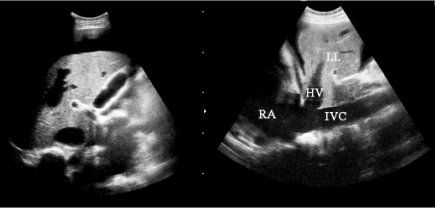

13.淤血性肝硬化者可见到下腔静脉和肝静脉内径明显增宽(图23-8)。

图23-8 淤血性肝硬化声像图

下腔静脉和肝静脉内径明显增宽,伴腹水